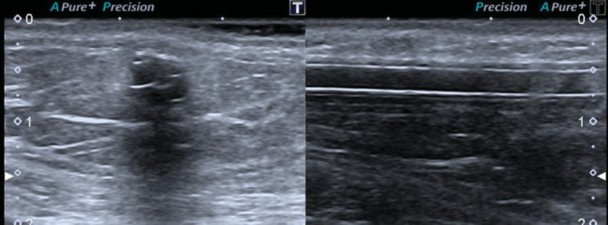

Se comunica un caso de una paciente de sexo femenino de 59 años de edad que fue sometida a la realización del estudio mamográfico de cribado anual, con las incidencias habituales cráneo-caudal y oblicuo-medio-lateral bilaterales. Se trató de una mama con áreas dispersas de densidad fibroglandular, en la cual se observaron calcificaciones gruesas de disposición lineal en la mama derecha proyectadas en el plano glandular profundo de los cuadrantes internos, con una solución de continuidad en el sector medio (►Fig. 1). Se recogieron los antecedentes clínico-ginecológicos de la misma, quien refirió la presencia de una válvula de derivación ventrículo peritoneal como tratamiento de una hidrocefalia de origen congénito. Posteriormente se realizó ecografía focalizada constatándose la presencia de imágenes de aspecto tubular continua con calcificaciones anulares (►Fig. 2).

Ecografía focalizada de los cuadrantes internos de la mama derecha, donde se visualiza una imagen de aspecto tubular.